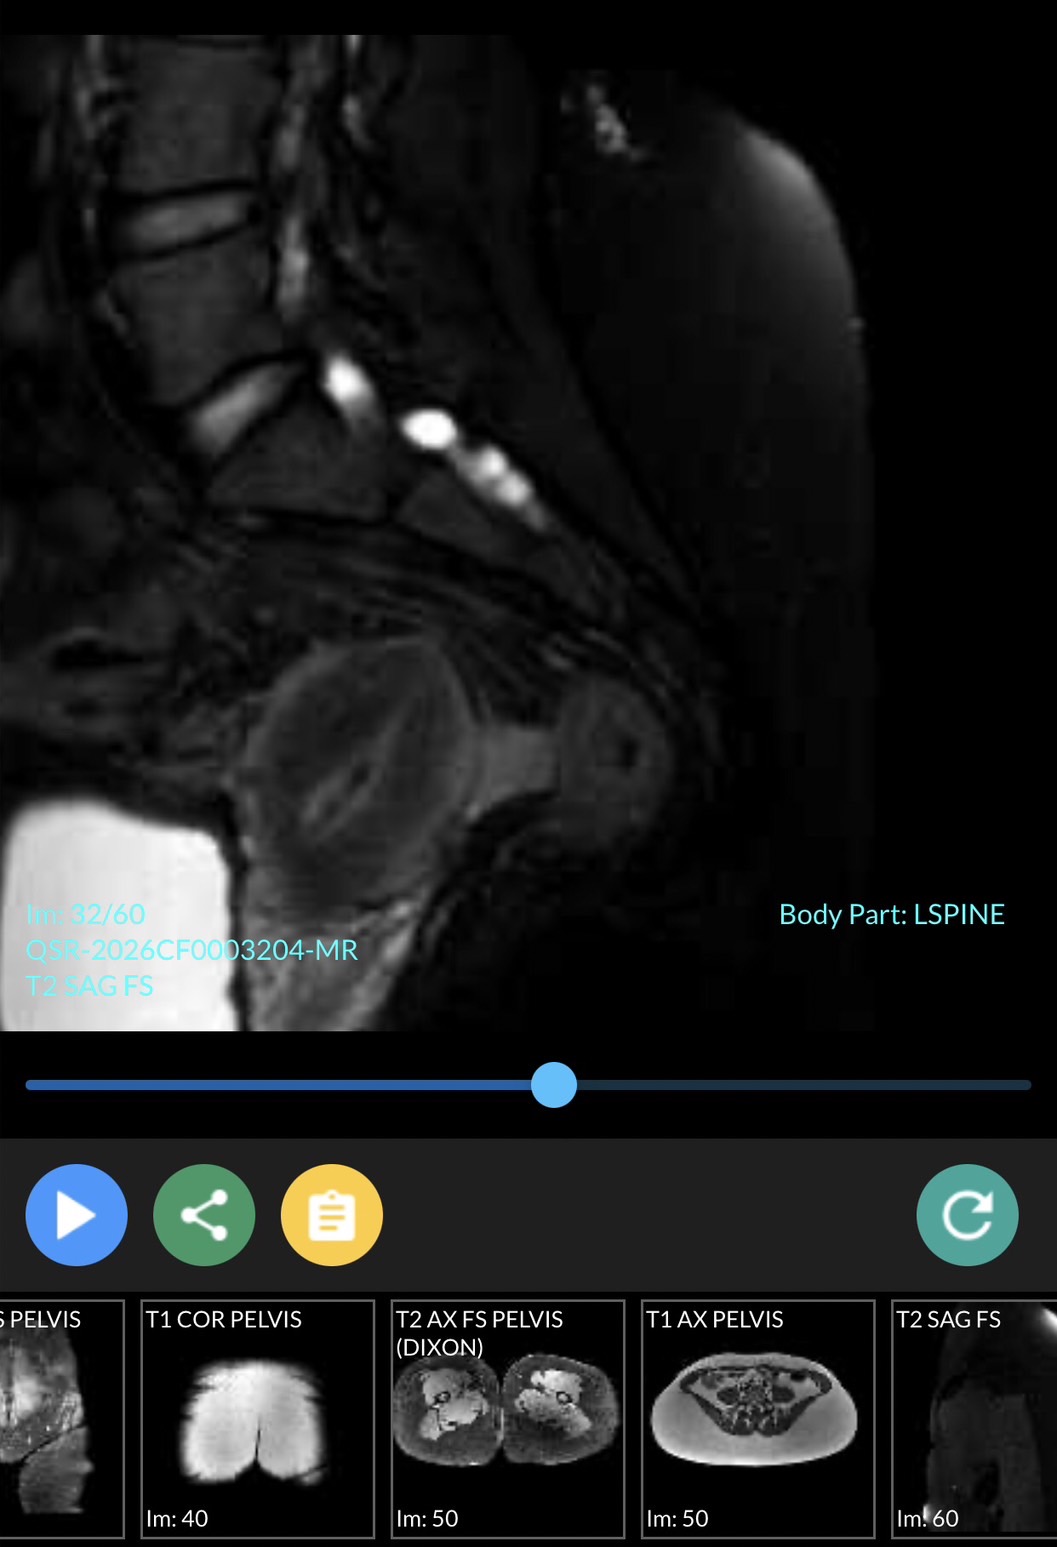

มีใครช่วยดูภาพ MRI Pelvis ของเราได้ไหมค่ะ

เรามีอาการทางประสาท ปวดแสบปวดร้อนที่กล้ามเนื้อขาอ่อน ชาขาลงเท้าเป็นบางครั้ง ส่วนมาจะเจ็บๆคันเหมือนโดนมดแดงไฟกัด บริเวณขาอ่อนด้านใน บางทีก๋กล้ามเนื้อสะโพกกับขาหนีบล็อกหกเกร็ง สะโพกรู้สึกหกเกร็งขาดความยืดหยุ่นเหมือนหนังยางที่ยึดแล้วมันปริแตกเป็นริ้ว เพราะหมดสภาพ บางทีก็แสบบริเวณกล้ามเนื้อเหนือหัวเข่า เรากำลังตามหาผู้ใจบุณช่วยวิเคราะห์ผล MRI ให้เราได้หลังไมค์มาเลนค่ะ เรายินดีส่งไฟล์ที่เป็น Full Version ให้ทางไลน์

จากรูปจุดขาวๆก้อนเล็กคืออะไรค่ะ